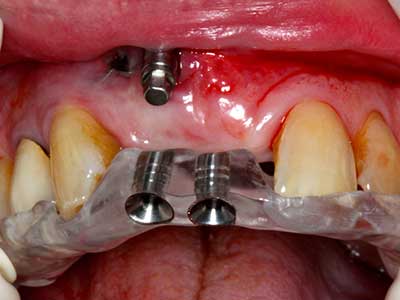

Quando le procedure chirurgiche vengono eseguite sull'osso nelle immediate vicinanze di strutture sensibili, come vasi sanguigni o nervi, gli strumenti rotanti pongono un rischio significativo di lesione iatrogena. I dispositivi piezoelettrici possono essere utili per la preparazione delle coperture ossee e la rimozione del tessuto duro in prossimità dei nervi, in particolare per la loro esposizione dopo una lesione iatrogena, ma anche durante la lateralizzazione dei nervi per le procedure di resezione e ricostruzione o il posizionamento di impianti (figg. 17-20). Il contatto leggero tra puntina piezoelettrica e nervo non causa generalmente danni, ma se si procede senza prestare attenzione con movimenti a sega o raccordi con residui di substrati ossei possono verificarsi danni al nervo temporanei o anche permanenti. Il rischio di danno, tuttavia, è considerato sostanzialmente inferiore al rischio presente utilizzando seghe o frese (Pereira, Gealh et al. 2014).

Come dimostrato in passato, pressoché qualsiasi procedura chirurgica che interessa il tessuto osseo rappresenta una possibile indicazione per la piezochirurgia. Quindi, per la preparazione del segmento mobile nella distrazione osteogenetica (figg. 23-25) e nell'osteotomia con tecnica a sandwich si utilizzano appositi raccordi per non danneggiare l'apporto sanguigno alla sezione della cresta, elemento essenziale per la corretta esecuzione di entrambe le tecniche (Gonzalez-Garcia, Diniz-Freitas et al. 2008).

Per la rimozione di un impianto, è possibile preparare una copertura dell'osso vestibolare da sostituire dopo la rimozione della vite dell'impianto, per conservare il contorno della cresta alveolare.